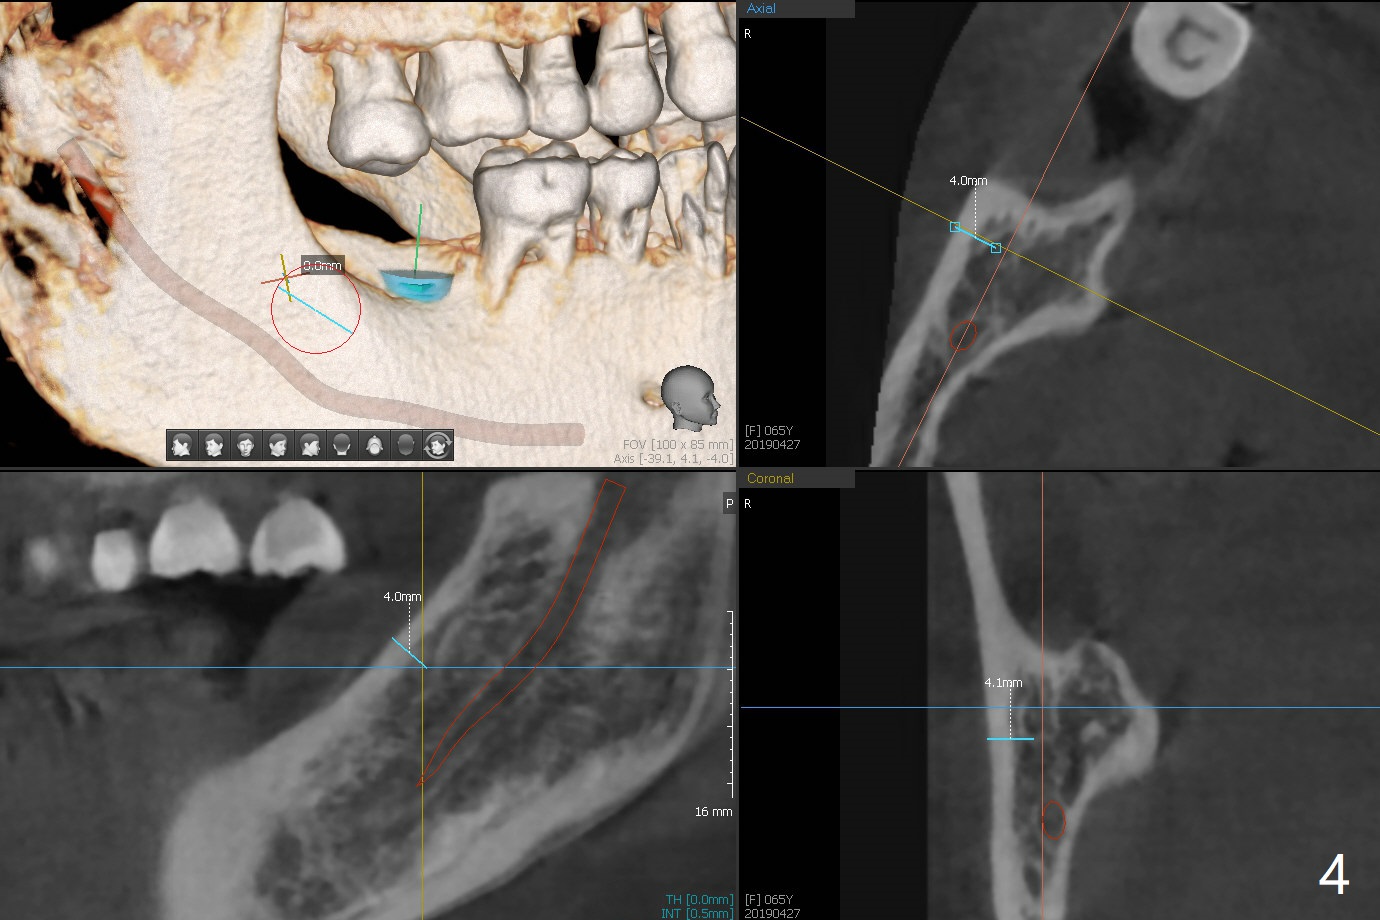

Socket Preservation Post Exfoliation

A 65-year-old woman seeks treatment after exfoliation of #18 (Fig.1). It appears important to have implants at #18 and 31 for longevity of restoration or implants at fractured teeth (*). The implant restoration at #31 will have challenge because of the supraeruption of the opposing tooth (arrow). The socket at #18 is large, shallow (Fig.2) and not healing. After debridement, bone graft will be placed, followed by 6 month membrane. Space maintenance will be installed for periodontal dressing stability. Prepare PRF if the vein is large enough.

To increase bone density, use a large 8/9 mm trephine bur to harvest ramus block graft on the right with depth of 3 mm (Fig.4 red circle) after SRP in the lower arch and transfer to #18 socket (Fig.3 pink), fixed in place with a screw (probably 6 or 8 mm tenting one, yellow) after filling the socket with particulate bone graft (Vanilla, white circle).